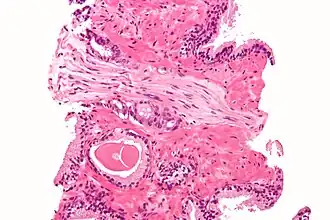

Micrograph demonstrating perineural invasion of prostate cancer. H&E stain.

Cancer can spread by invading the spaces around nerves. This is particularly common in head and neck cancer, prostate cancer and colorectal cancer. Multiple sclerosis is a disease associated with extensive nerve damage. It occurs when the macrophages of an individual's own immune system damage the myelin sheaths that insulate the axon of the nerve.